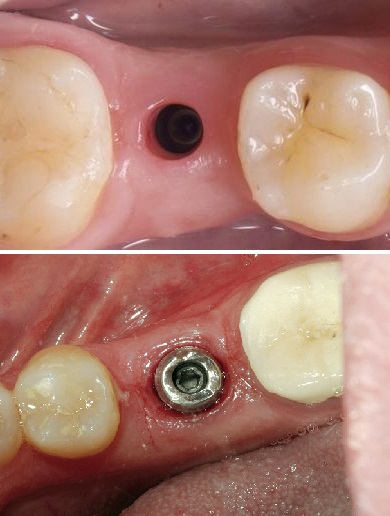

Trụ phục hình cá nhân hóa bằng Zirconia

Hình ảnh gắn trụ phục hình và gắn răng sứ. Một trường hợp trồng implant răng cửa bằng giải pháp DCT tại Lạc Việt Intech.

Một trường hợp sử dụng trụ phục hình các nhân hóa bằng zirconia.

So sánh với một trường hợp sử dụng trụ phục hình sản xuất sẵn (đã được mài mặt ngoài để xóa hình thể tròn).